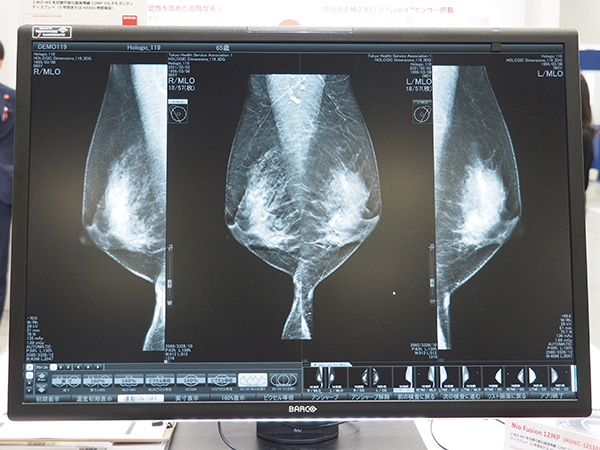

バルコは例年,医用画像表示ディスプレイや映像配信・画像統合ソリューション,サージカルディスプレイソリューションなどをテーマ別に展示している。ITEM2023の医用画像表示ディスプレイコーナーでは,高輝度PACS向けディスプレイ「Nio Color 2MP」(MDNC-2521)/「Nio Color 3MP」(MDNC-3521)やディスプレイの遠隔モニタリングを可能にする「Medical QAWeb Enterprise」を初披露した。また,画像配信ソリューションコーナーでは,非圧縮IPビデオソリューション「Nexxis」による映像配信環境を再現したほか,独自の画像合成機能を搭載した4K 55インチ大型サージカルディスプレイなどの新製品がアピールされた。

また,超高精細12MPカラーディスプレイ「Nio Fusion 12MP」や同社初のデジタルパソロジー(病理学)向け27インチ8MP超高解像度ディスプレイ「MDPC-8127」など,幅広いラインアップが展示された。

超高精細12MPカラーディスプレイ「Nio Fusion 12MP」などの既存製品も展示された